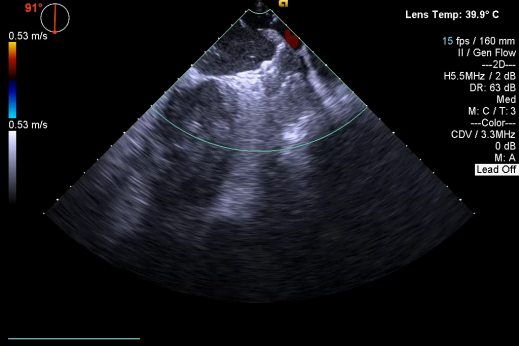

▲释放后,DSA与TEE观察均无残余分流

其中首场公开演示的左心耳血栓封堵病例具有极高难度,患者术前TEE显示左心耳血栓形成伴机化,血栓位于心耳中段,近中端絮状物明显。封堵机会只有一次,选型和操作稍有失误,都会增加手术风险。因此手术采取全麻,并安装了抗栓塞脑动脉保护装置,以减少术中风险。通过TEE引导下测量左心耳大小以及确认左心耳血栓位置,李岳春教授凭借自身丰富经验最终决定使用LAmbre 2632型号,采用推送式植入法将左心耳血栓牢牢锁死于远端,并且封堵器一次成型,封堵效果极佳,结束后取出脑保护装置,均未见血栓,顺利完成了此台高难度的手术,获得了学员们的一致认可。